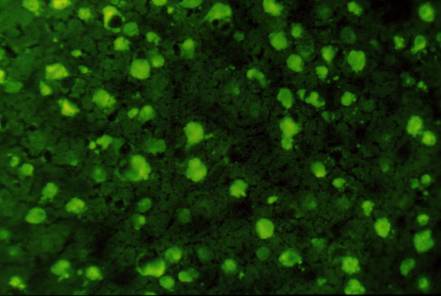

Figure 1 : Anticorps anti-nucléaires, aspects de la fluorescence. a)

homogène ; b) nucléolaire ; c) moucheté ; d) centromérique.

Photo : Immunologie clinique, 1991, J. Brostoff, Ed DeBoeck Université